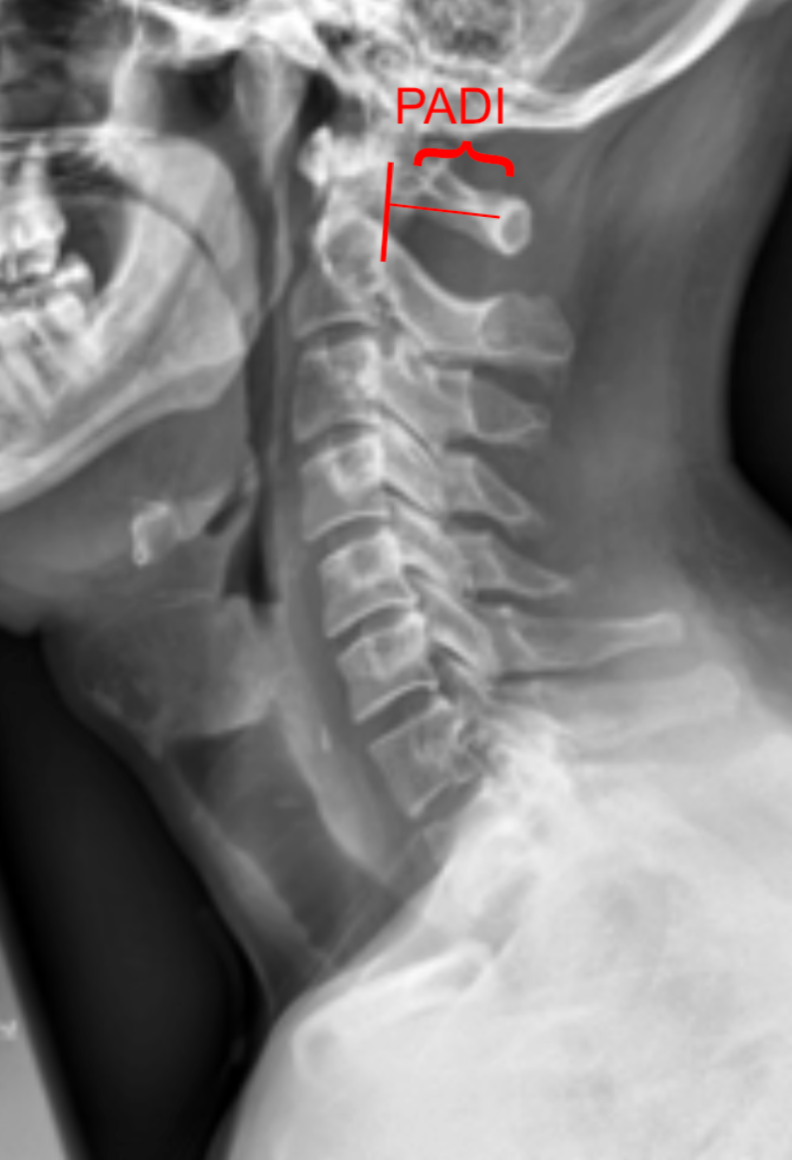

Posterior Atlantodental Interval (PADI)

The Posterior Atlantodental Interval (PADI), also known as the space available for the cord (SAC), is the distance between the posterior surface of the odontoid process (dens) and the anterior surface of the posterior arch of the atlas (C1).

It represents the effective canal diameter at the atlantoaxial level and is a critical measurement for evaluating cervicomedullary compression. A decreased PADI suggests potential spinal cord impingement, even when the atlantodental interval (ADI) is within normal limits.

• Obtain a neutral lateral cervical spine X-ray (as shown in provided images).

• Identify the posterior surface of the odontoid process (dens).

• Identify the anterior surface of the posterior arch of C1 (atlas).

• Draw a line along each of these two surfaces.

• Measure the shortest perpendicular distance between them—this is the PADI.